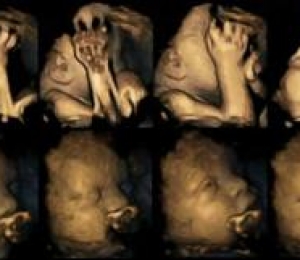

Doctorul Nadja Reissland a studiat radiografiile 4D a 20 de mame care aşteptau un copil, 4 dintre ele fiind fumătoare, înregistrând mii de mişcări minuscule ale fătului în săptămâna 24, 28, 32 şi 26 de sarcină.

În urma acestui studiu, s-a descoperit că bebeluşii nenăscuţi al celor patru mame fumătoare se ating pe faţă în mod frecvent, mai des ca ceilalţi. În mod normal, bebeluşii se mişcă în burtă pe măsură ce cresc şi deprind controlul membrelor.

Rezultate doctorului Reissland indică că mamele care fumează pot îngreuna dezvoltarea sistemului nervos al fătului.